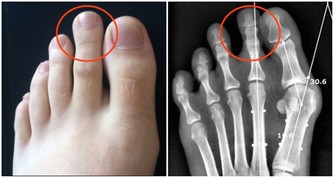

很多人,或許有個疑問,那就是,戒菸後肺部真的還能恢復健康嗎?

專家表示,戒菸後肺部是可以慢慢恢復的。若在35歲前成功戒菸,你的預期壽命會同常人一樣。

戒菸24小時後: 血液系統、血壓及心臟健康等會逐漸恢復正常。

戒菸48小時後: 消除大部分尼古丁,嗅覺與味覺也逐漸變更好。

戒菸3~9個月後:呼吸問題變好了,肺部開始逐漸恢復健康。

戒菸1年以後:冠狀動脈疾病風險降低50%

戒菸5年後:中風的風險降低至和不抽煙的人同樣水平。

戒菸10年後:患肺癌的機率達到了正常吸煙人的一半。

戒菸15年後:患冠心病的風險同不抽煙的人一樣。死亡的風險也恢復到了和不抽煙人一樣。

所以,任何時候戒菸都不晚,為了自己和家人的健康,嘗試著努力戒菸吧~